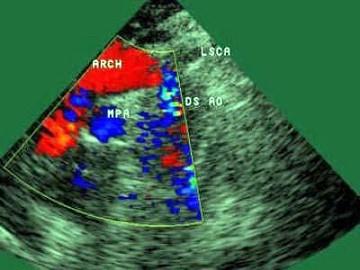

问题 患者,男,8岁,因腹痛伴呕吐1个月,持续加重1周入院,行心脏及腹部超声检查,下图为胸骨上窝大动脉长轴切面,根据图像显示,该患者最有可能诊断为?(?)

选项 A.动脉导管未闭 B.主-肺动脉间隔缺损 C.主动脉缩窄 D.肺动脉狭窄 E.室间隔缺损

答案 C